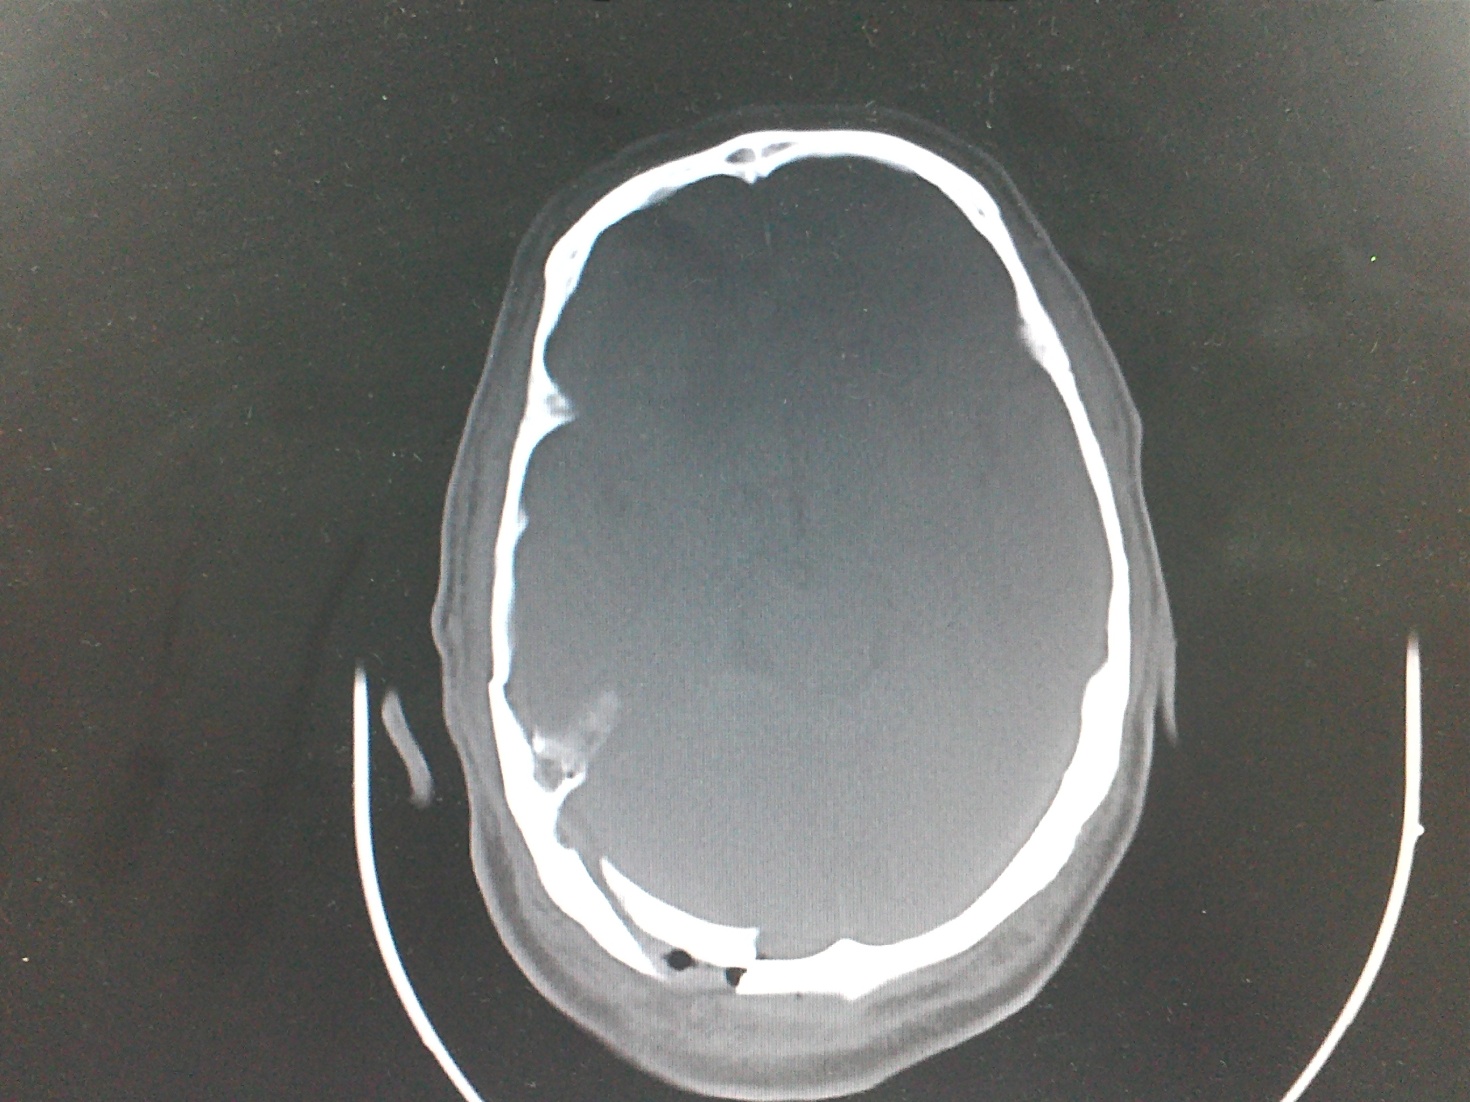

Fractura deprimida cerrada de la fosa posterior en un anciano

Skull fractures are primary lesions of the skull. Posterior fossa fractures are rare, it is considered that the multiple layers of muscle makes it less easy to fracture.We report the case of a male of 72 years who presented head injury during assault.A literature search revealed only two case report of closed depressed fracture of the posterior fossa.Descargas